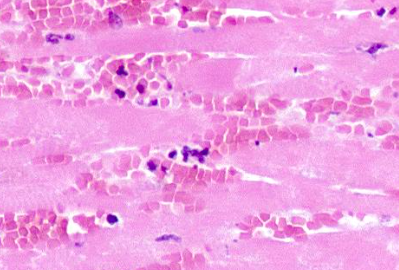

When would this histopatholigcal slide from an MI likely to have occurred

Less than 1 day

Less than 7 days

1-3 week

3-6 weeks